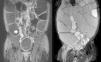

A 38-year-old man with a 20-year history of Crohn's disease presented with weight loss, abdominal distention and vomiting. He had been medicated from diagnosis with 5-aminosalicylic acid and later with azathioprine, which he intentionally stopped 2 years later. His last colonoscopy, dating 5 years before, revealed severe ulceration in the ascending and sigmoid colon. On physical examination the patient was severely emaciated. His abdomen was distended, non-tender, and showed markedly reduced bowel sounds (Fig. 1). His vital signs were normal. Laboratory tests showed mild anemia (12.7g/dL) and C-reactive protein (22mg/L), with normal serum electrolytes. Upright abdominal X-ray showed severely distended bowel loops (Fig. 2), later confirmed by abdominal computed tomography. These findings raised our suspicion for the presence of megacolon. As the patient did not presence signs of systemic toxicity we adopted a conservative approach with intravenous steroids, antibiotics, fluid support, daily abdominal X-ray and evaluation by a dedicated surgeon. On the third day of admission, a colonoscopy was performed showing an ulcerated stricture in the terminal ileum that did not allow passage of the endoscope (Fig. 3). The colon showed no signs of active inflammation. Unexpectedly, MRI-enterography showed severe distention (up to 8cm) of a wide segment of the small bowel proximal to a long stricture. The large bowel appeared not to be significantly distended (Fig. 4). The anatomopathologic examination of the small bowel biopsies showed severe transmural inflammation and architectural distortion compatible with Crohn's Disease. There were also multiple nuclear and cytoplasmic inclusions compatible with cytomegalovirus (CMV) infection. As there was suggestion that the stricture could partially be inflammatory and that the patient might benefit from medical therapy, he was started on ganciclovir and Infliximab. Unfortunately, by the 14th week of therapy there was no significant improvement. Due to progressive weight loss, the patient was scheduled for surgery. Examination of the resection specimen confirmed the long 11cm stricture with severe distention of both the small bowel (11cm) and ascending colon (9.5cm).